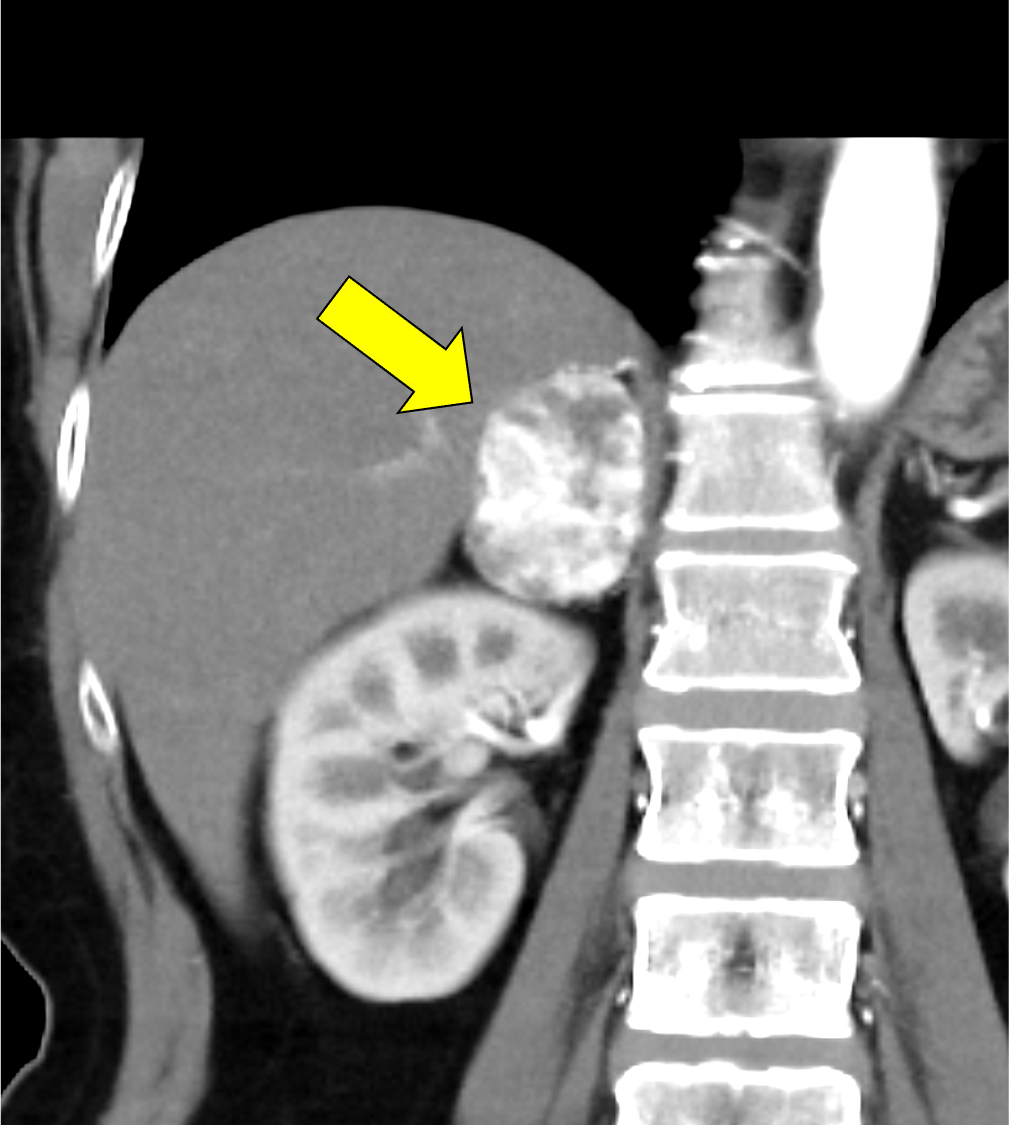

60歳代、 女性、 46kg、 右副腎褐色細胞腫

右副腎多血性腫瘍の術前精査

本例は、偶発的に指摘された右副腎腫瘍である。高血圧はあるが内服せず経過観察されている患者で、1cm/5年程度の非常に緩徐な増大を示す多血性の腫瘍を認める。腫瘍はI-123MIBGシンチ陰性であり、内分泌内科での精査においてもホルモン産生を疑う所見に乏しく、褐色細胞腫よりも海綿状血管腫が疑われていた。しかし、増大傾向があり破裂や出血のリスクなども考慮されて手術の方針となった。手術中に血圧の変動を認め、病理で褐色細胞腫の診断となった。

褐色細胞腫は副腎髄質に存在するクロム親和性細胞に由来する腫瘍で、カテコールアミンなど種々の生理活性物質を産生する。ダイナミック造影で動脈相での強い濃染と持続する造影効果が特徴とされ、サイズが大きい病変は嚢胞変性や出血、壊死を伴うことが多い。かつては、臨床的に褐色細胞腫が疑われる場合、ヨード造影剤の投与はカテコールアミンの過剰放出を誘発し、高血圧クリーゼを引き起こす可能性があるため原則禁忌とされていた。しかし、現在汎用されている非イオン性・低浸透圧性造影剤であればこの現象は起こらないとの報告もあり、European Society of Urogenital Radiology Guidelines on Contrast Media, ver 10.0では、「経静脈的ヨード造影剤の投与をする場合でも特別な準備の必要はない」と記載されている。イオプロミドの電子添文上は、禁忌にはなっていないものの、「慎重に投与すること」との記載になっている。本例では、血管腫疑いとして合計5回の造影CTが行われているが、血圧変動や頭痛、動悸などの症状は一度も認められなかった。

本例の画像所見として、褐色細胞腫としてダイナミック造影の濃染パターンは典型的ともいえたが、大きさの割に変性が乏しい点、MIBGシンチでの核種集積に乏しい点、ホルモン産生に乏しい点など非典型的な要素が複数存在し、海綿状血管腫を除外しきれなかった。なお、褐色細胞腫はRET遺伝子変異による多発性内分泌腺腫症(multiple endocrine neoplasia;MEN)type 2A・2B、VHL遺伝子によるvon Hippel-Lindau病、NF1遺伝子による神経線維腫症1型に生じることが知られているが、これらの疾患を想起させるような他病変は本例には見つかっていない。